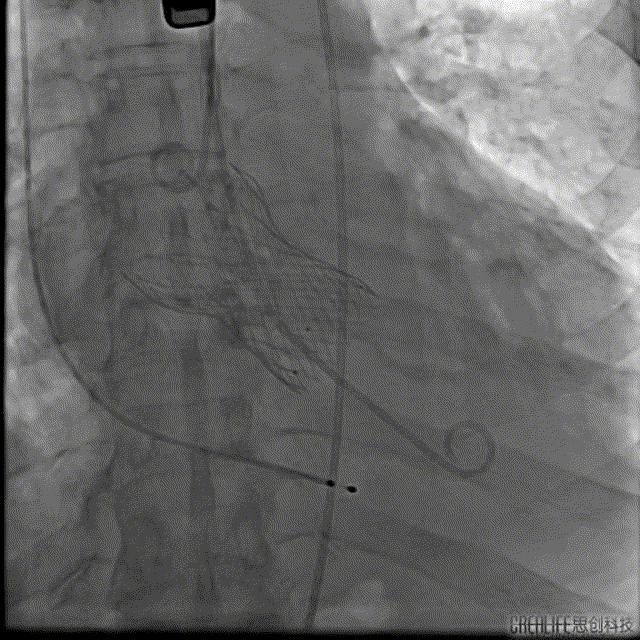

根部造影

造影大量反流

最后一枪造影